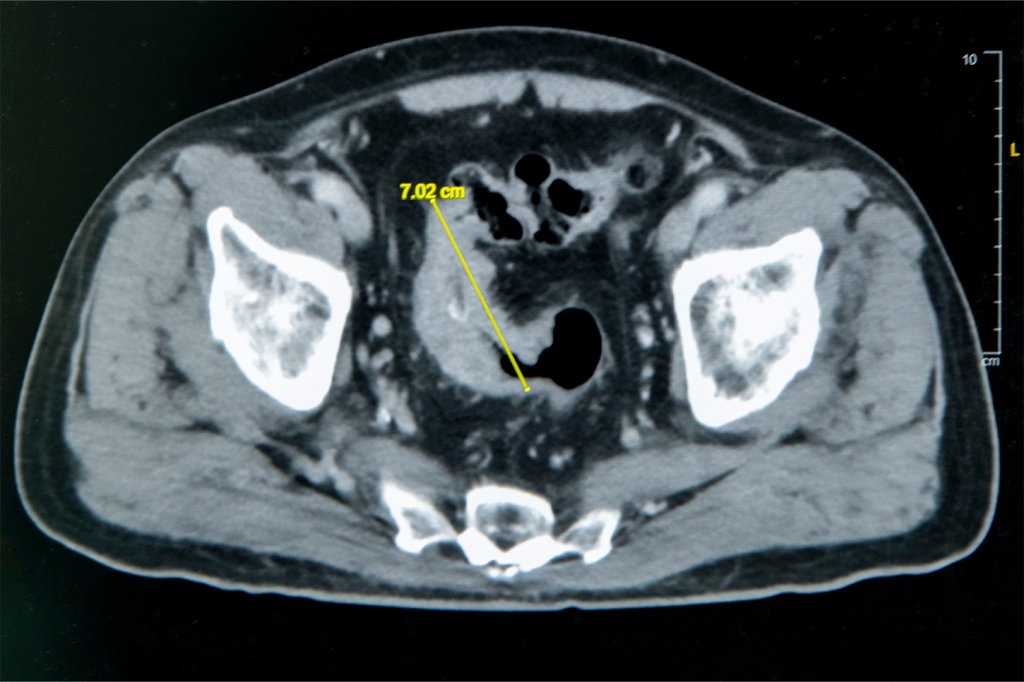

雲林七旬翁便秘 竟是7公分大腸癌惹禍

雲林縣七旬翁由於便秘,到雲基接受舒眠大腸鏡檢查,結果顯示大腸有異常病灶,經評估需手術治療。為讓父親手術過程減少疼痛、恢復更快,女兒選擇轉至彰基醫學中心接受治療,由大腸直腸外科張譽耀主任操刀,採用單孔達文西機械手臂SP系統手術。-